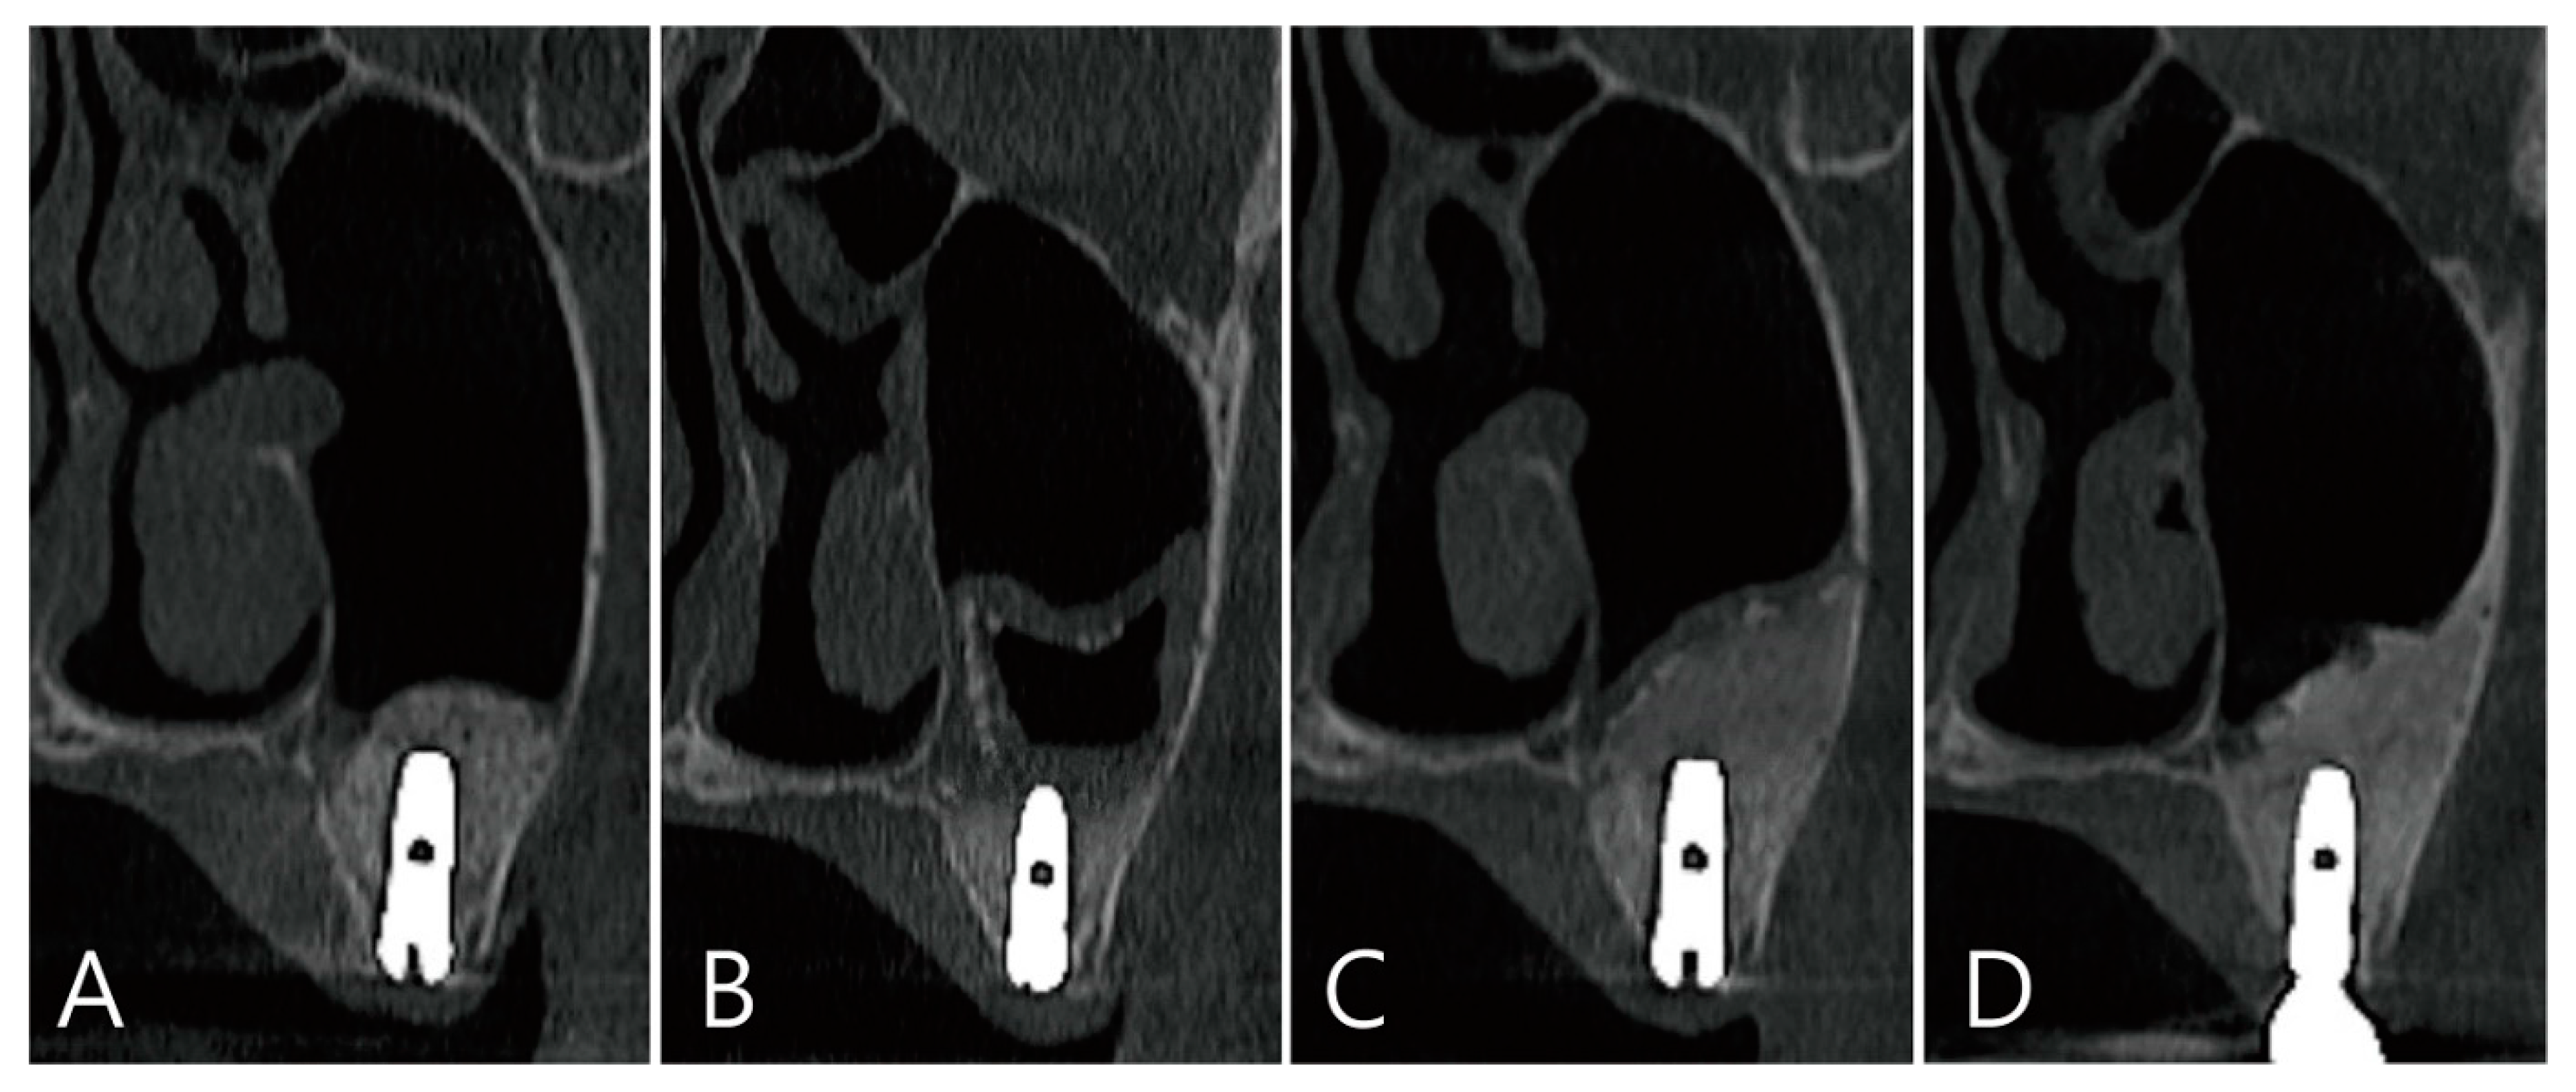

In the CBCT image taken immediately after the maxillary sinus bone graft, a thickened sinus membrane was observed on top of the bone graft material, and there was no leakage of the bone graft material (Figure 8A,B). In the CBCT image taken 6 months after surgery, a large grafting void was observed in the bone graft area which showed a cystic appearance (Figure 8C,D).

Figure 8. Case 3. CBCT images taken immediately after maxillary sinus bone graft: (A) On the panoramic image of CBCT, a thickened mucosa on the sinus floor was observed above the bone graft; (B) Coronal image of the CBCT. (C,D) Images of the CBCT taken 6 months after surgery: (C) in the coronal image of the CBCT, large grafting voids with a cystic appearance were observed; (D) a well-defined radiolucent appearance was observed on an axial image of the CBCT.